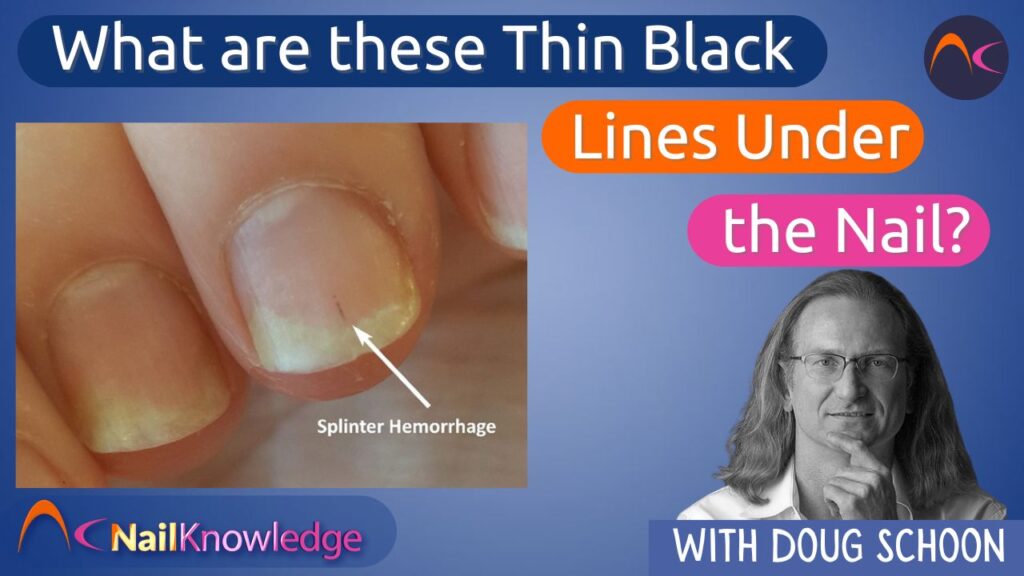

Dermatoscopia Unha: Exame Essencial

Para entender o que está acontecendo com aquela linha preta na unha, a dermatoscopia é uma aliada poderosa. Ela vai além do que o olho nu vê.

Visualização Ampliada

O dermatoscópio permite uma visão ampliada da estrutura da unha. Isso ajuda a identificar padrões que podem indicar a causa do risco escuro na unha.

Diagnóstico Diferencial

Com a dermatoscopia unha, é possível diferenciar entre melanoníquia estriada benigna e sinais que podem indicar algo mais grave. É um exame rápido e indolor.

Prevenção e Segurança

Esse exame é crucial para um diagnóstico precoce. Ele aumenta as chances de sucesso no tratamento de qualquer condição ungueal.